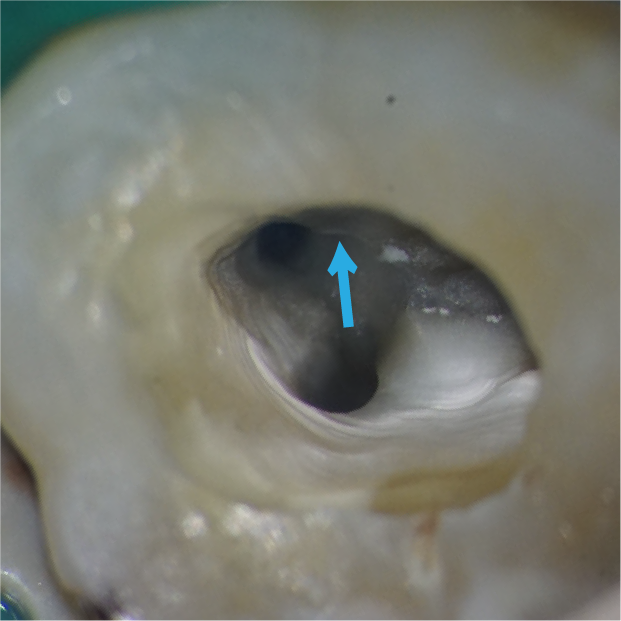

矢印の部分には、これまで見つかっていなかった細い根の管(根管)があります。マイクロスコープで大きく拡大して見ることで、わずかな入口を慎重に探し出し、丁寧に開くことができます。

その結果、隠れていた根管を安全に見つけ出し、適切な治療を行うことができました。